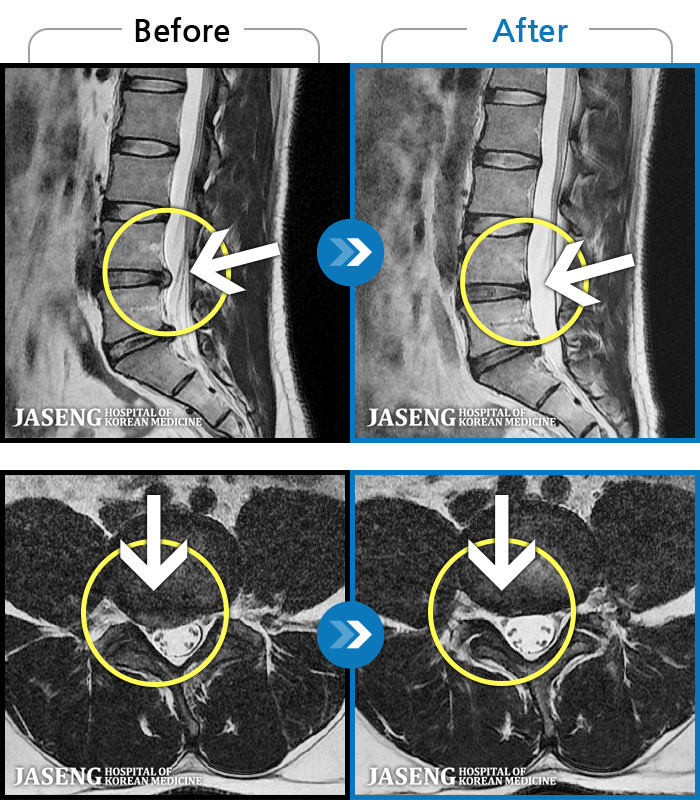

[뱸] 19.11.28~25.05.06